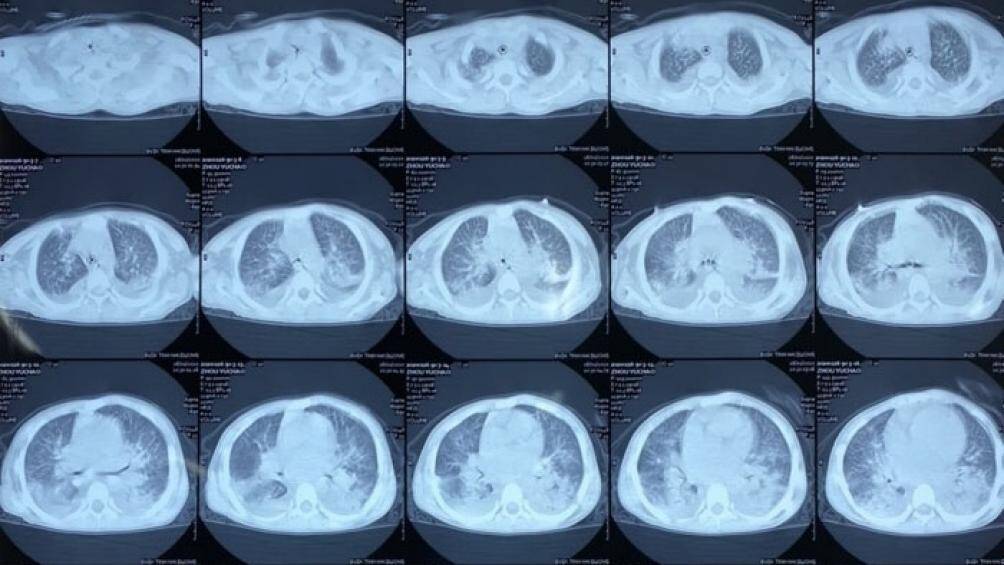

Qua chẩn đoán hình ảnh, hội chẩn, bác sĩ chẩn đoán bệnh nhi suy hô hấp, viêm phổi, có tiền sử suy thượng thận bẩm sinh, chưa loại trừ khả năng phù phổi.

Kết quả chẩn đoán hình ảnh bệnh nhân nghi nhiễm virus corona. Ảnh: Vietnamnet |